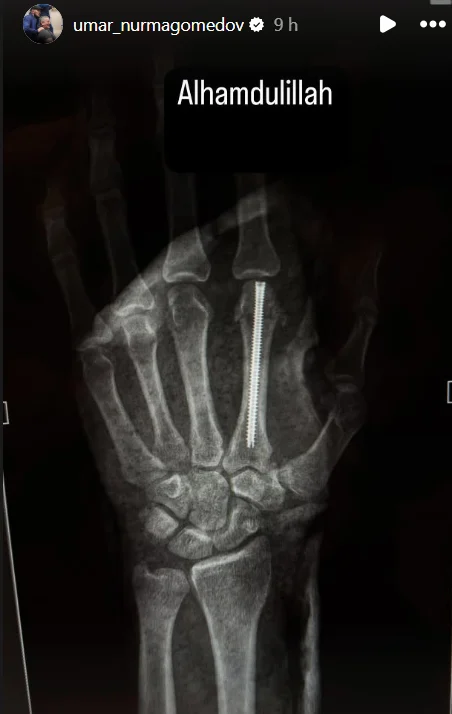

La lesión sufrida por Umar Nurmagomedov en su derrota ante Merab Dvalishvili en el evento coestelar de UFC 311, el pasado sábado (18), llevó al ruso a la mesa de operaciones. Este jueves (23), el peso gallo (61 kg) utilizó sus redes sociales para publicar una imagen radiográfica de su mano izquierda después de someterse a la operación.

En la imagen, es posible ver que, durante la cirugía reconstructiva, se insertó un tornillo en el hueso metacarpiano del dedo índice de la mano izquierda del peleador. La fractura, según el equipo de Nurmagomedov y el propio atleta, se habría producido al comienzo de la pelea contra el campeón Merab Dvalishvili.